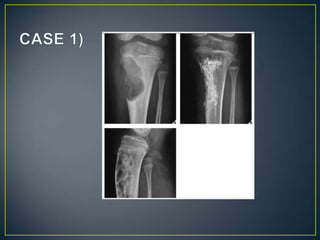

• If radiographs are suggestive of a malignant bone tumor,

MRI or CT should be used next to evaluate both the

intraosseous extent of the tumor and the extraosseous

involvement of the soft tissues.

• If there is no definite evidence of soft-tissue extension,

then CT is superior to MRI.

• If the radiographs suggest cortical destruction and softtissue mass, then MRI would be the preferred modality .

• Identification of tumor bone within or adjacent to the area

of destruction should alert the radiologist to the possibility

of osteosarcoma/reactive sclerosis.

• Osteosarcoma-cloudy - cotton like fluffy deposits.